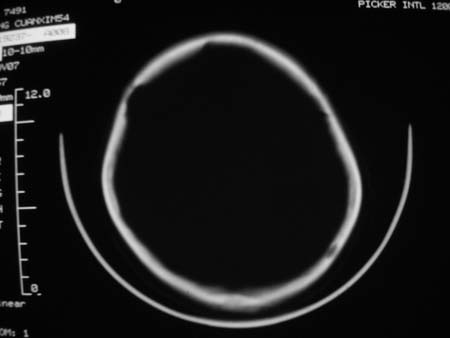

男,54岁,十天前被钢管打伤头顶部,现自述头部不适,视物模糊,并于两天前发觉右枕部有包块,既往未有明显异常.

颅骨多处骨质不完整,内板变薄,右侧额颞部局部呈“穿凿样”骨质缺损,相应区硬膜外密度略增高。多考虑:骨嗜酸性肉芽肿!

颅骨多处骨质不完整,内板变薄,右侧额颞部局部呈“穿凿样”骨质缺损,相应区硬膜外密度略增高。多考虑:骨髓瘤或骨嗜酸性肉芽肿!

颅骨多处骨质不完整,内板变薄,右侧额颞部局部呈“穿凿样”骨质缺损,缺损骨质边缘锐利无硬化,相应区硬膜外密度略增高。多考虑:骨嗜酸性肉芽肿!

颅骨多处骨质不完整,内板变薄,右侧额颞部局部呈“穿凿样”骨质缺损,相应区硬膜外密度略增高。多考虑:骨髓瘤或骨嗜酸性肉芽肿!10天前受伤,不会在2天前才发现头部包块,估计与外伤无关.